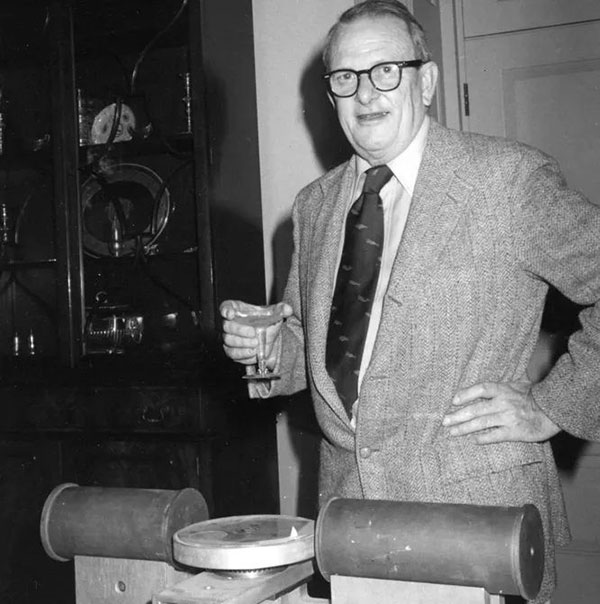

В 1956 году Рональд Н. БРЕЙСВЕЛЛ использовал похожий на преобразование Радона метод для восстановления карты солнечной радиации. В 1959 году Уильям ОЛДЕНДОРФ, невролог из Калифорнийского университета в Лос-Анджелесе, предложил идею сканирования головы с помощью рентгеновских лучей и возможности реконструкции картин рентгеноплотности плоскости, проходящей через голову. Наблюдая за автоматическим аппаратом для отбраковки обмороженных фруктов, он заметил, что рентгеновские снимки ногтей, окружённых другими ногтями, невозможно сделать под одним углом.

В 1961 году Олдендорф создал прототип с вращающимся источником рентгеновского излучения и детектором, который позволял получать рентгеновские снимки ногтей. В своей статье он описал основную концепцию, которую Аллан Маклеод КОРМАК использовал для разработки математики, лежащей в основе компьютерной томографии.

В октябре 1963 года Олдендорф получил американский патент на «устройство с лучистой энергией для исследования отдельных областей внутренних объектов, скрытых плотным материалом», за который он разделил премию Ласкера с Хаунсфилдом в 1975 году.

Несмотря на важные достижения экспериментов Бокажа, Валлебоны, Ольдендорфа и других исследователей, ни один из них не добился значительного успеха в своём деле. Ольдендорф выразил свою твёрдую убеждённость в создании системы, способной получить поперечное отображение неоднородности радиоплотности внутри объектов неправильной формы, таких как голова. Чтобы эти разработки могли быть реализованы на практике, учёным пришлось дождаться необходимых изменений в электронике.